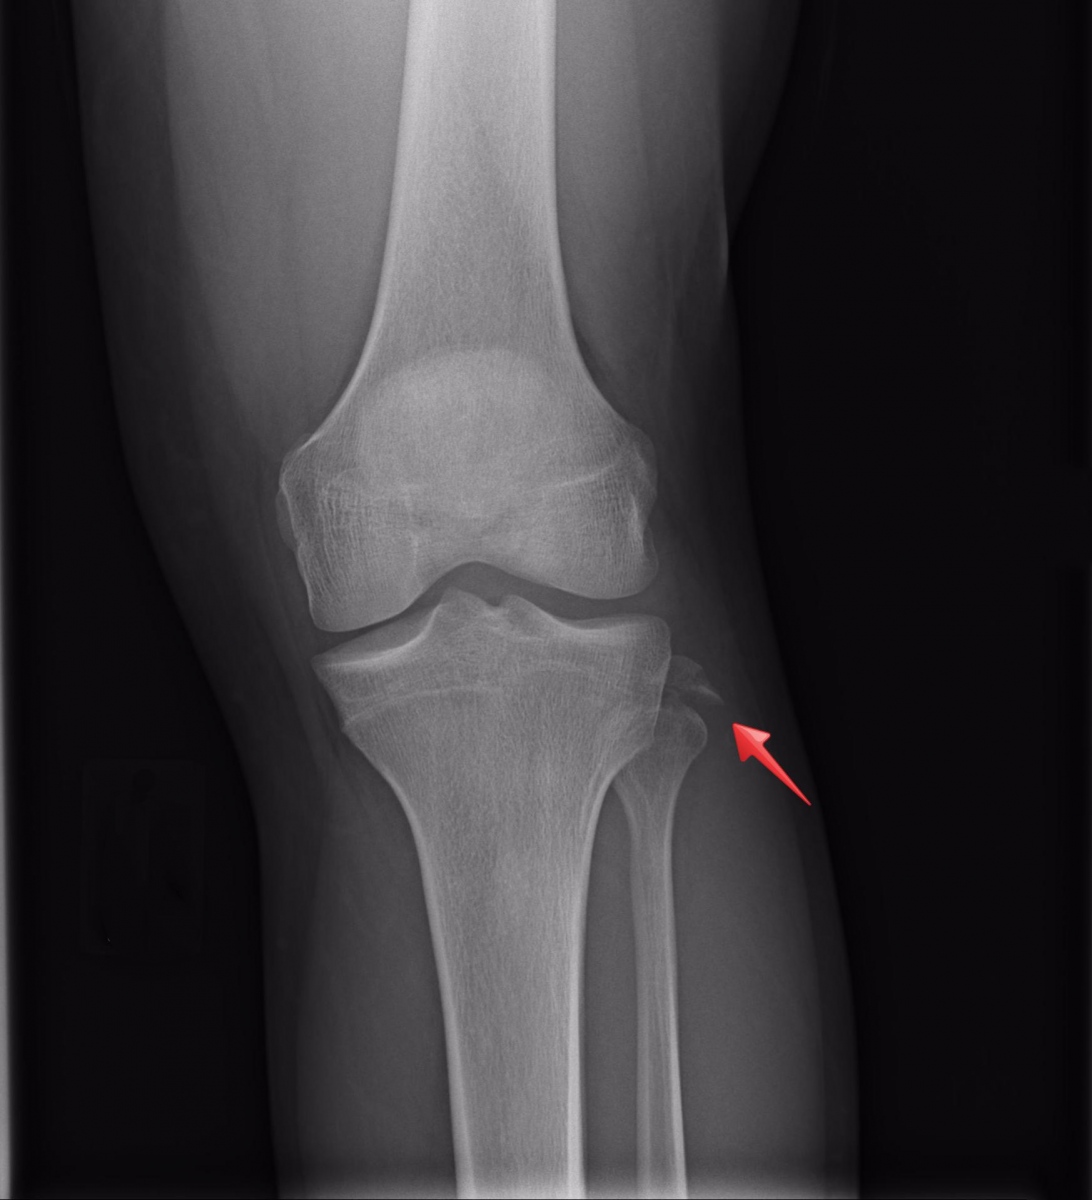

Answer: Avulsion fracture of the fibular styloid process, compatible with an arcuate sign.

Fibular Styloid Fracture/Arcuate Sign

- Mechanism is direct trauma to the anteromedial knee while in extension or sudden hyperextension; also seen in knee dislocations.

- Avulsion fracture at the proximal fibula at the insertion site of the arcuate ligament; 90% of fractures have disruption of the lateral collateral ligament

- Injury to other structures of the posterolateral ligamentous complex is also common.

- This injury is highly suspicious of an unstable knee joint and needs emergent orthopedic evaluation.

- Due to anatomic location of fracture, can also involve injury to peroneal nerve.